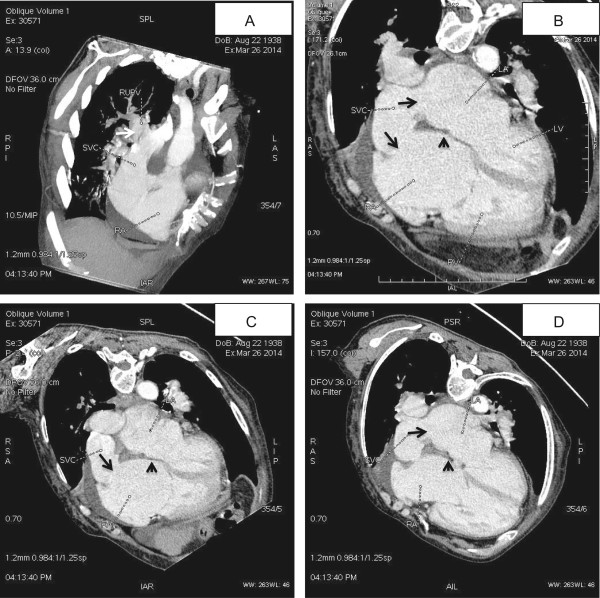

Pulmonary embolism was suspected and MCTA was performed then, which confirmed the diagnosis of PAPVC and SVD. The anatomical and morphological features of this congenital defect were clearly revealed by MCTA. The RUPV was unroofed and drained into the SVC at the level of the caval atrial junction (Figure 2A). The atrial septum was actually intact and no true atrial ASD was present (Figure 2B, C, D). The SVC overrode across the intact atrial septum and had bi-atrial connection (Figure 2B) with one opening connecting to the right atrium (Figure 2C) and another opening to the left atrium (Figure 2D).

Figure 2.

MCTA demonstrated a PAPVC associated with a SVD. A: The RUPV was unroofed and drained into the SVC at the level of the caval atrial junction (white arrow). B: The SVC had bi-atrial connection and overrode across the atrial septum (black arrow), and the atrial septum was actually intact (black triangle). C: The SVC had one opening connecting to the right atrium (black arrow); D: The SVC had another opening connecting to the left atrium (black arrow).